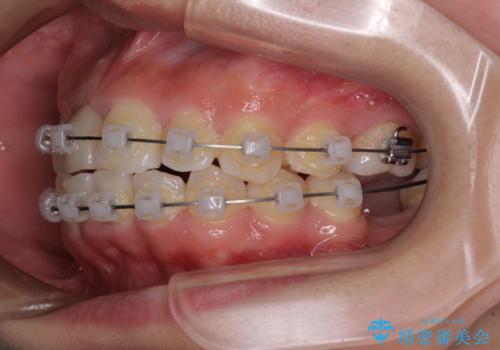

- 矯正装置

- クリアブラケット

- 放置した虫歯や抜いたままの奥歯、前歯のデコボコを気にして来院された患者様です。

口元の突出感は少なく、下顎の叢生は軽微なものであったので、叢生の強い上顎左右の小臼歯を1本ずつ抜歯し、ワイヤー装置にて矯正治療を行うこととしました。

矯正治療を行う前に、根管治療の必要な上顎前歯と下顎大臼歯の根管治療を行い、矯正治療の途中で下顎の欠損部にインプラント埋入することとし、矯正治療後に補綴治療を行うこととしました。